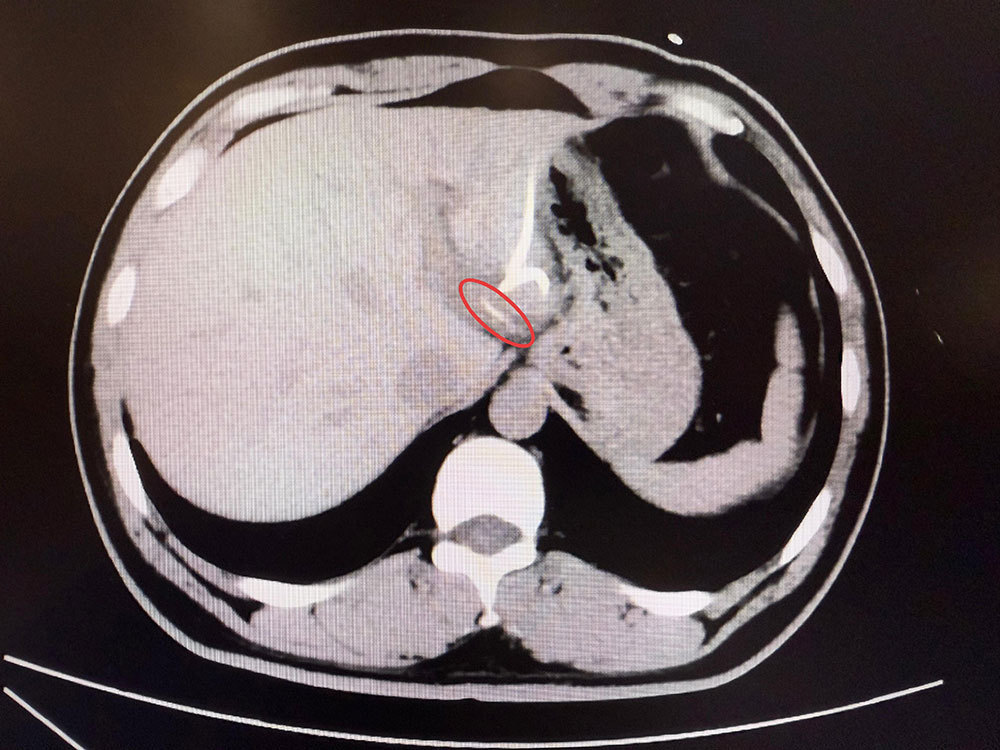

直到CT检查时,医生才惊讶地发现,李先生肝脏左叶靠近胃贲门处有一条细长的高密度影,形似鱼刺。原来,那根鱼刺在吞咽后穿透了胃壁,从贲门区域钻入肝脏,引发感染与脓肿。在简单进行肝脓肿介入穿刺引流后,当地外科医生评估后认为,要彻底清除异物,需要进行左半肝切除手术,但这对于李先生来说,创伤大、风险高,他难以接受。

患者李先生影像检查。本文图片均来自复旦大学附属中山医院